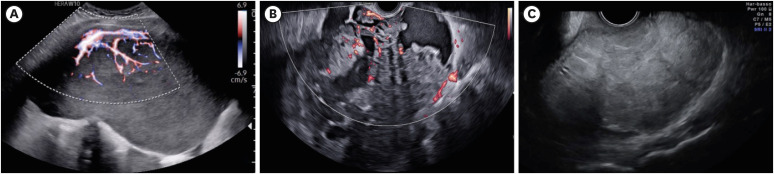

恶性卵巢生殖细胞瘤是一种罕见而多样的恶性肿瘤,约占所有卵巢癌的5%。主要影响年轻女性,这些肿瘤提出了独特的挑战,特别是在平衡有效治疗和生育能力的保护。早期诊断是常见的,因为肿瘤生长迅速,症状如腹痛和腹胀,当结合铂基方案的高化疗敏感性时,预后良好。保留生育能力的手术是I期疾病治疗的基础,通常随后进行密切监测,以尽量减少化疗的长期毒性。病理是诊断的关键,结合免疫组织化学标记来区分恶性卵巢生殖细胞肿瘤亚型,包括胚芽发育不良瘤、卵黄囊瘤和未成熟畸胎瘤。先进的成像方式,如超声、磁共振成像和计算机断层扫描对于分期、监测治疗反应和检测复发是必不可少的。尽管治愈率很高,但长期随访对于治疗晚期毒性(如性腺功能障碍和继发性恶性肿瘤)至关重要。复发性恶性卵巢生殖细胞肿瘤提出了重大的治疗挑战。高剂量化疗联合干细胞移植在某些病例中提供了希望,而二次细胞减少手术和放疗的作用仅限于特定适应症。新兴的靶向治疗和新方法,如针对KIT突变的异常生殖细胞瘤的KIT抑制剂,仍处于实验阶段,迄今为止报道的成功有限。恶性卵巢生殖细胞肿瘤的罕见性和异质性阻碍了大规模的研究工作,强调需要更深入地了解其分子和遗传景观,以开发更有效和个性化的治疗方法。